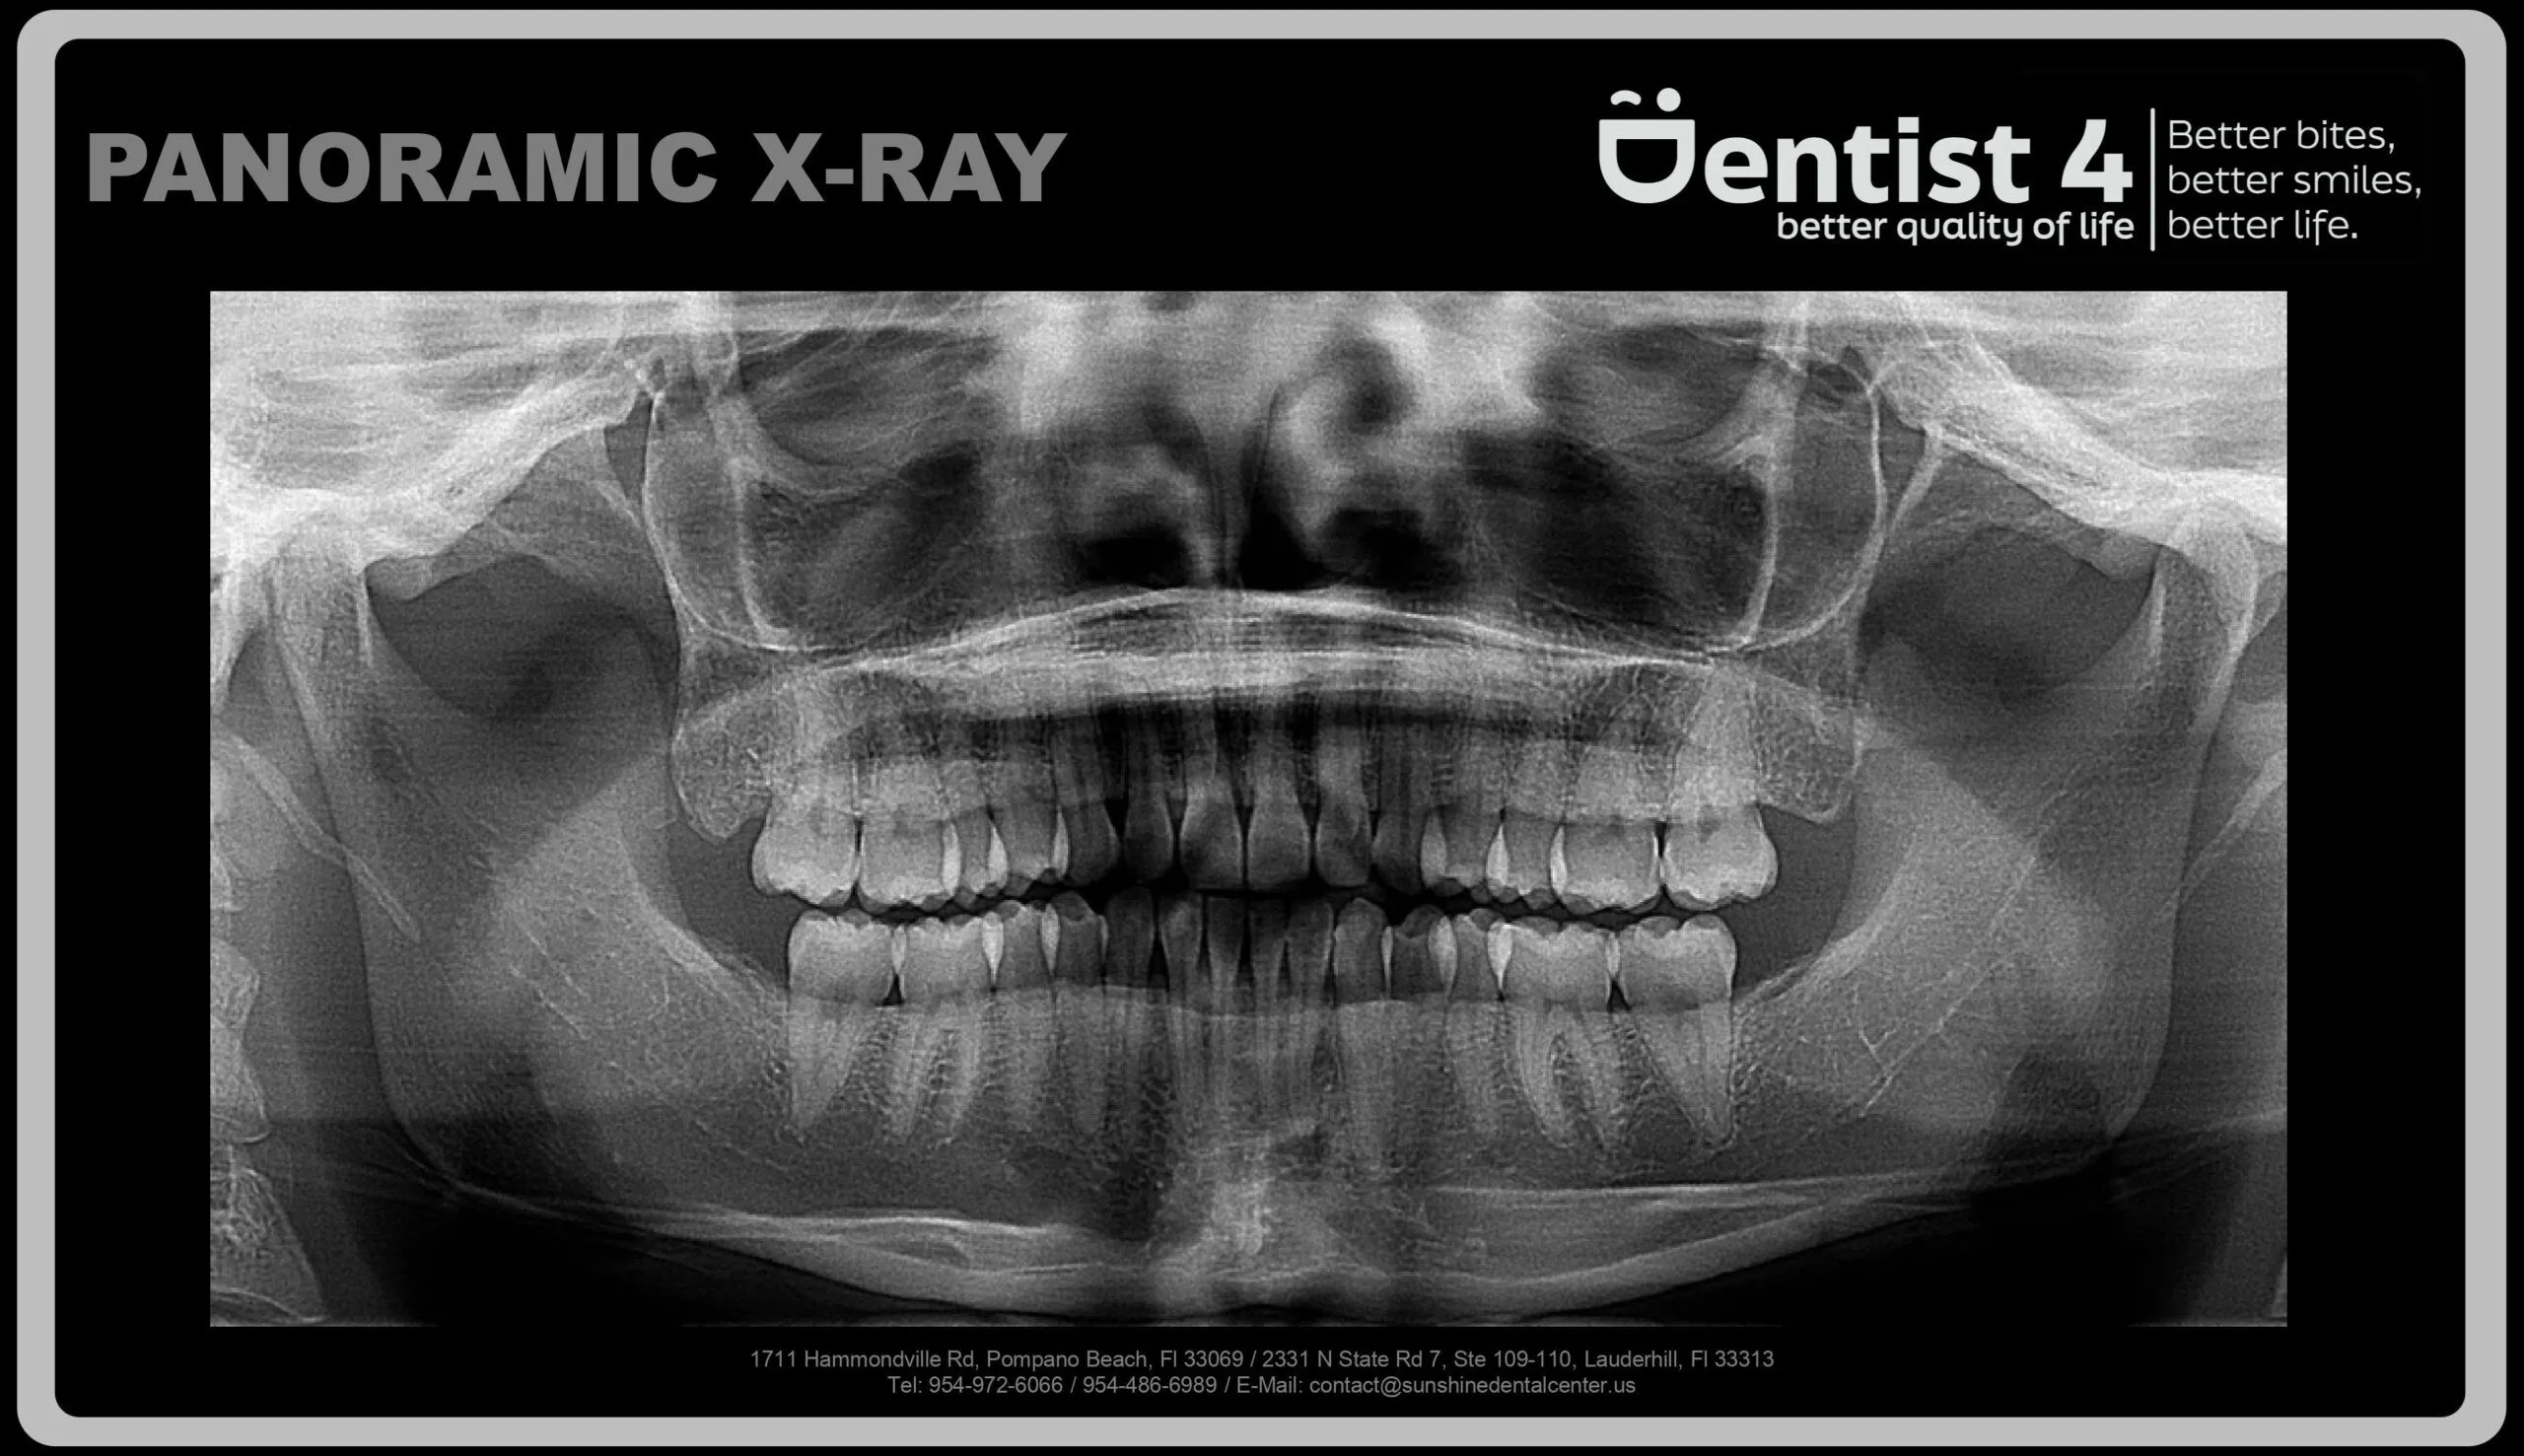

Panoramic X-ray: This X-ray captures the entire dentition, supporting bone, adjacent structures, and tooth positions. It offers a comprehensive view of the patient’s oral health.